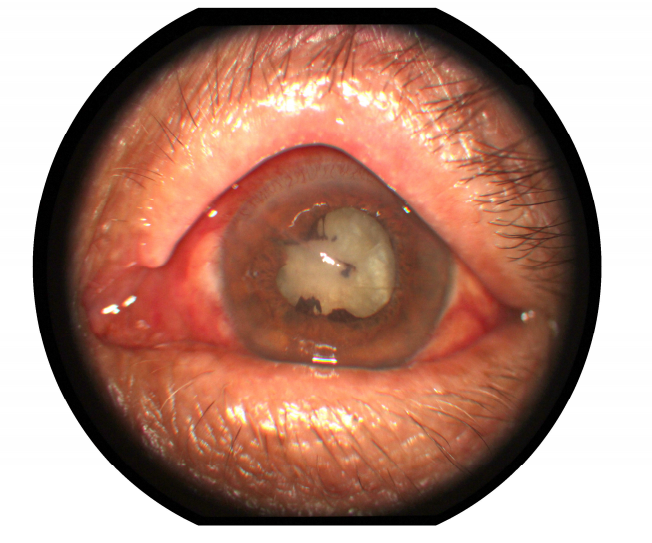

刘大爷左眼检查结果影像

“要直接摘掉眼球,我实在无法接受。”心急如焚的刘大爷打算去十堰市人民医院眼科试试。到达科室时,刘大爷的左眼还在缓缓渗着血水。经检查他的左眼完全感觉不到光线,并且眼内炎症严重,已经化脓。“泥土里存在很多细菌,附着在锄头上,又随着铁屑被带入患者的眼睛。”十堰市人民医院眼科Ⅱ病区主任柯峰针对刘大爷的病情分析道。

术前眼眶CT,可见金属异物正位于患者左眼视网膜上,情况十分凶险。